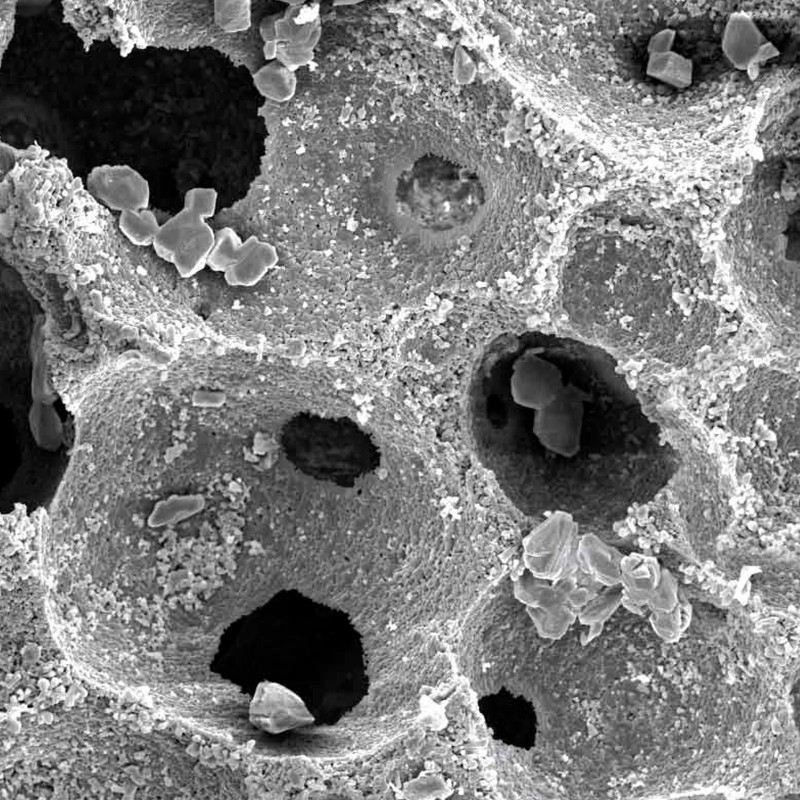

Maxresorb® inject es una pasta ósea sin endurecimiento y lista para el uso compuesta de gel de nano-HA de base acuosa y partículas de Maxresorb®. Debido a su composición específica, las propiedades viscosas de maxresorb® inject permiten una forma, moldeado y ajuste perfectos y una completa adhesión a la superficie ósea circundante del defecto.

Viscosidad y moldabilidad

Debido a su carácter viscoso que no endurece Maxresorb inject se moldea fácilmente en el lugar del defecto. Se adapta a los contornos de la superficie y proporciona el máximo contacto óseo.

Maxresorb® inject es una pasta ósea sin endurecimiento y lista para el uso compuesta de gel de nano-HA de base acuosa y partículas de Maxresorb®. Debido a su composición específica, las propiedades viscosas de maxresorb® inject permiten una forma, moldeado y ajuste perfectos y una completa adhesión a la superficie ósea circundante del defecto.

Viscosidad y moldabilidad

Debido a su carácter viscoso que no endurece Maxresorb inject se moldea fácilmente en el lugar del defecto. Se adapta a los contornos de la superficie y proporciona el máximo contacto óseo.

Biofuncionalidad

Las partículas de nano-HA, ofrecen una superficie muy grande para las interacciones celulares y son rápidamente reabsorbibles.

El componente nano-HA, que representa aproximadamente el 80% del material, se reabsorbe en un plazo de 6-8 semanas.

Los gránulos maxresorb ayudan a mantener el volumen a lo largo del tiempo.

Maxresorb inject es una masilla ósea sin endurecimiento que promueve una rápida regeneración ósea mediante el crecimiento interno de vasos sanguíneos y células a través de su estructura porosa.